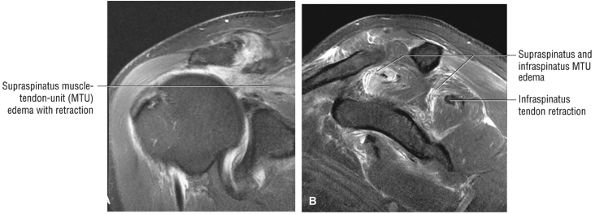

FIGURE 8.102 ● (A) The anterior undersurface of the acromion and the coracoacromial ligament form the coracoacromial arch. The subacromial subdeltoid bursa facilitates the passage of the rotator cuff and proximal humerus under the coracoacromial arch. (B) A superior axial image shows the anterior-to-posterior extent of the coracoacromial (CA) ligament perpendicular to the supraspinatus tendon. The fluid in the subacromial-subdeltoid bursa represents fluid between two serosal surfaces in contact with each other. One serosal surface is contributed by the undersurface of the coracoacromial arch and deltoid, and the other serosal surface is on the bursal side of the cuff.

|

![]() |